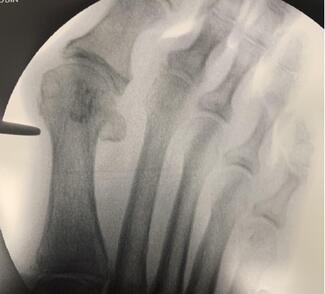

William D. Fishco, DPM, MS, FACFAS; Mahsa Agha Jafari, DPM, AACFAS

Fifth metatarsal fractures are relatively common injuries, but athletes in particular require a unique approach. Here the authors share their experience and evidence from the literature, including classification, examination, imaging and...